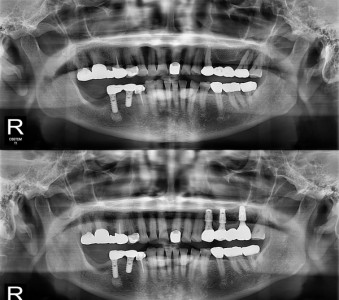

以成果证明实力。

国际摩牙齿科

真实临床案例